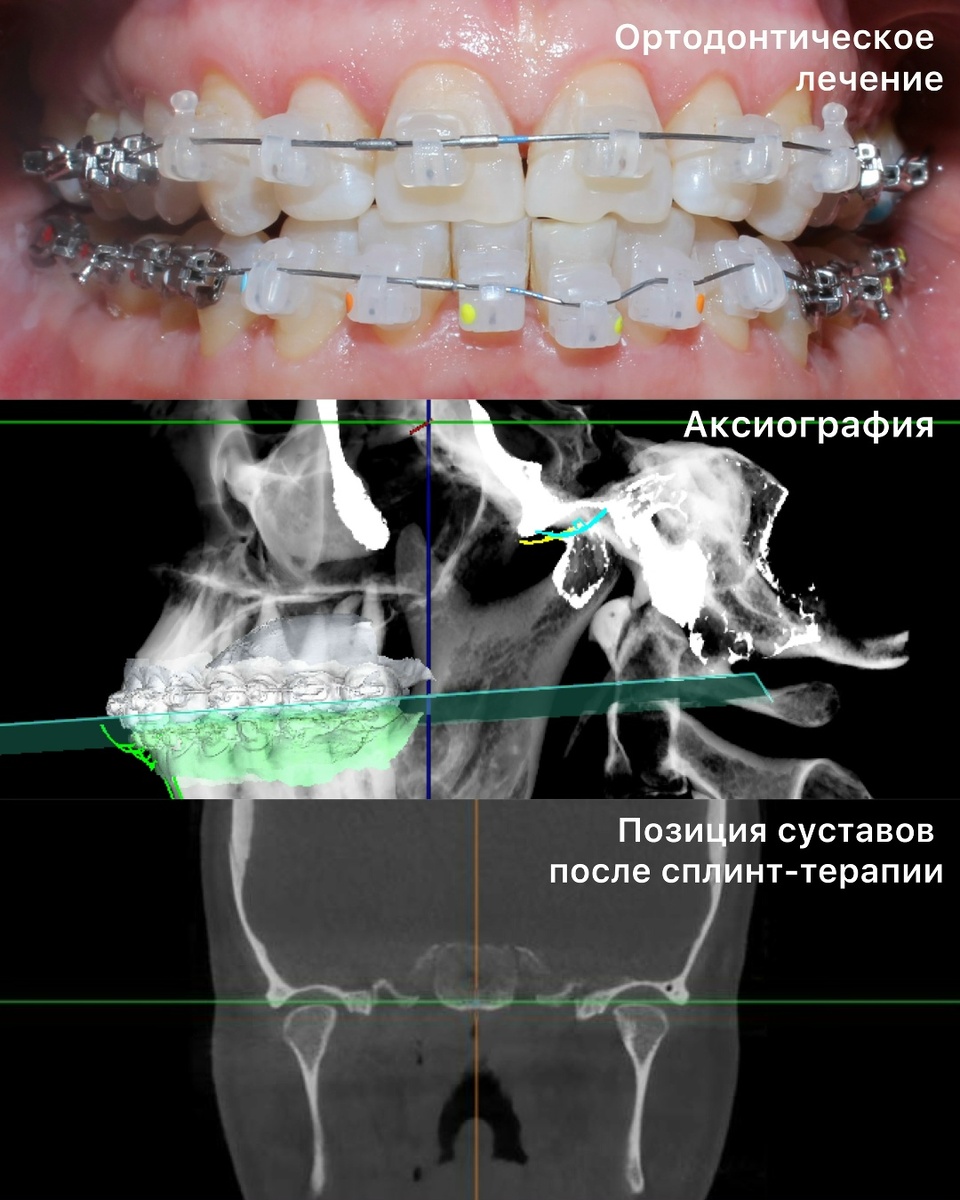

Пациентка поступила к нам на реабилитацию с клиникой компенсированных, но уже давно запущенных функциональных расстройств. После диагностики мы приступили к реабилитации прикуса. Заменили все несостоятельные ортопедические конструкции и начали исправление прикуса. Дойдя до финального этапа ортодонтического лечения, провели аксиографию, нашли ЦС(центральное соотношение) и с помощью сплинт-терапии устранили щелчок в суставе. Получив новое положение челюсти, закрепили результат временным протезированием с контрольными снимками КТ и МРТ. И только после этого перешли к финишному этапу - тотальной реконструкции прикуса с применением ультратонких ортопедических конструкций. Выбор конструкций исходил из принципа максимального сохранения своих тканей, поэтому даже на жеватеных зубах мы использовали адгезивный протокол, так как главной задачей стояло максимальное сохранение своих тканей, в частности эмали. После окончания такого рода работ всегда хочется поблагодарить наших пациентов за доверие,

После диагностики мы приступили к реабилитации прикуса. Заменили все несостоятельные ортопедические конструкции и начали исправление прикуса. Дойдя до финального этапа ортодонтического лечения, провели аксиографию, нашли ЦС(центральное соотношение) и с помощью сплинт-терапии устранили щелчок в суставе. Получив новое положение челюсти, закрепили результат временным протезированием с контрольными снимками КТ и МРТ.

И только после этого перешли к финишному этапу - тотальной реконструкции прикуса с применением ультратонких ортопедических конструкций.